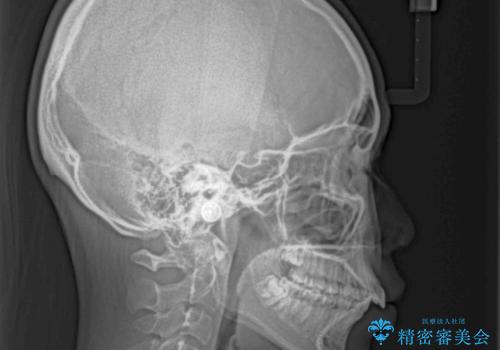

骨格的な出っ歯を抜歯矯正で改善 横顔の印象が劇的に変化

- 飛び出した上顎前歯と、閉じにくい唇、口元の突出した印象の横顔を気にして来院された患者様です。

骨格的な上顎前突であり、上下前歯の前後的な距離が大きいため、上顎は左右第一小臼歯を、下顎は左右第二小臼歯をそれぞれ2本抜歯することで前歯が接触するようにし、さらには奥歯の咬み合わせも、より理想的な状態へ近づけていくこととしました。

3年以上はかかる難症例であるため、表側のワイヤー装置にて治療を行うこととしました。

事前の予想通り、長期間を要する治療となりましたが、横顔の印象が劇的に変化し、患者様には大変満足していただきました。